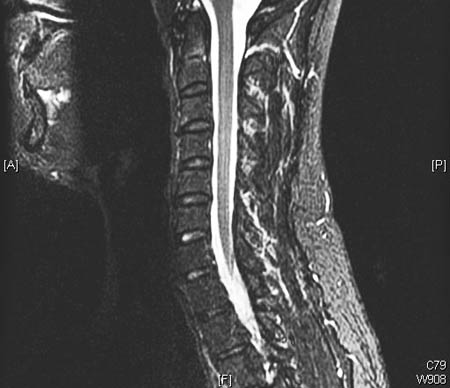

Doença degenerativa da coluna cervical

Ressonância nuclear magnética (RNM) cervical (T2 sagital) com doença articular degenerativa moderada, mas sem compressão significativa da medula espinhal

Dennis A. Turner, MA, MD